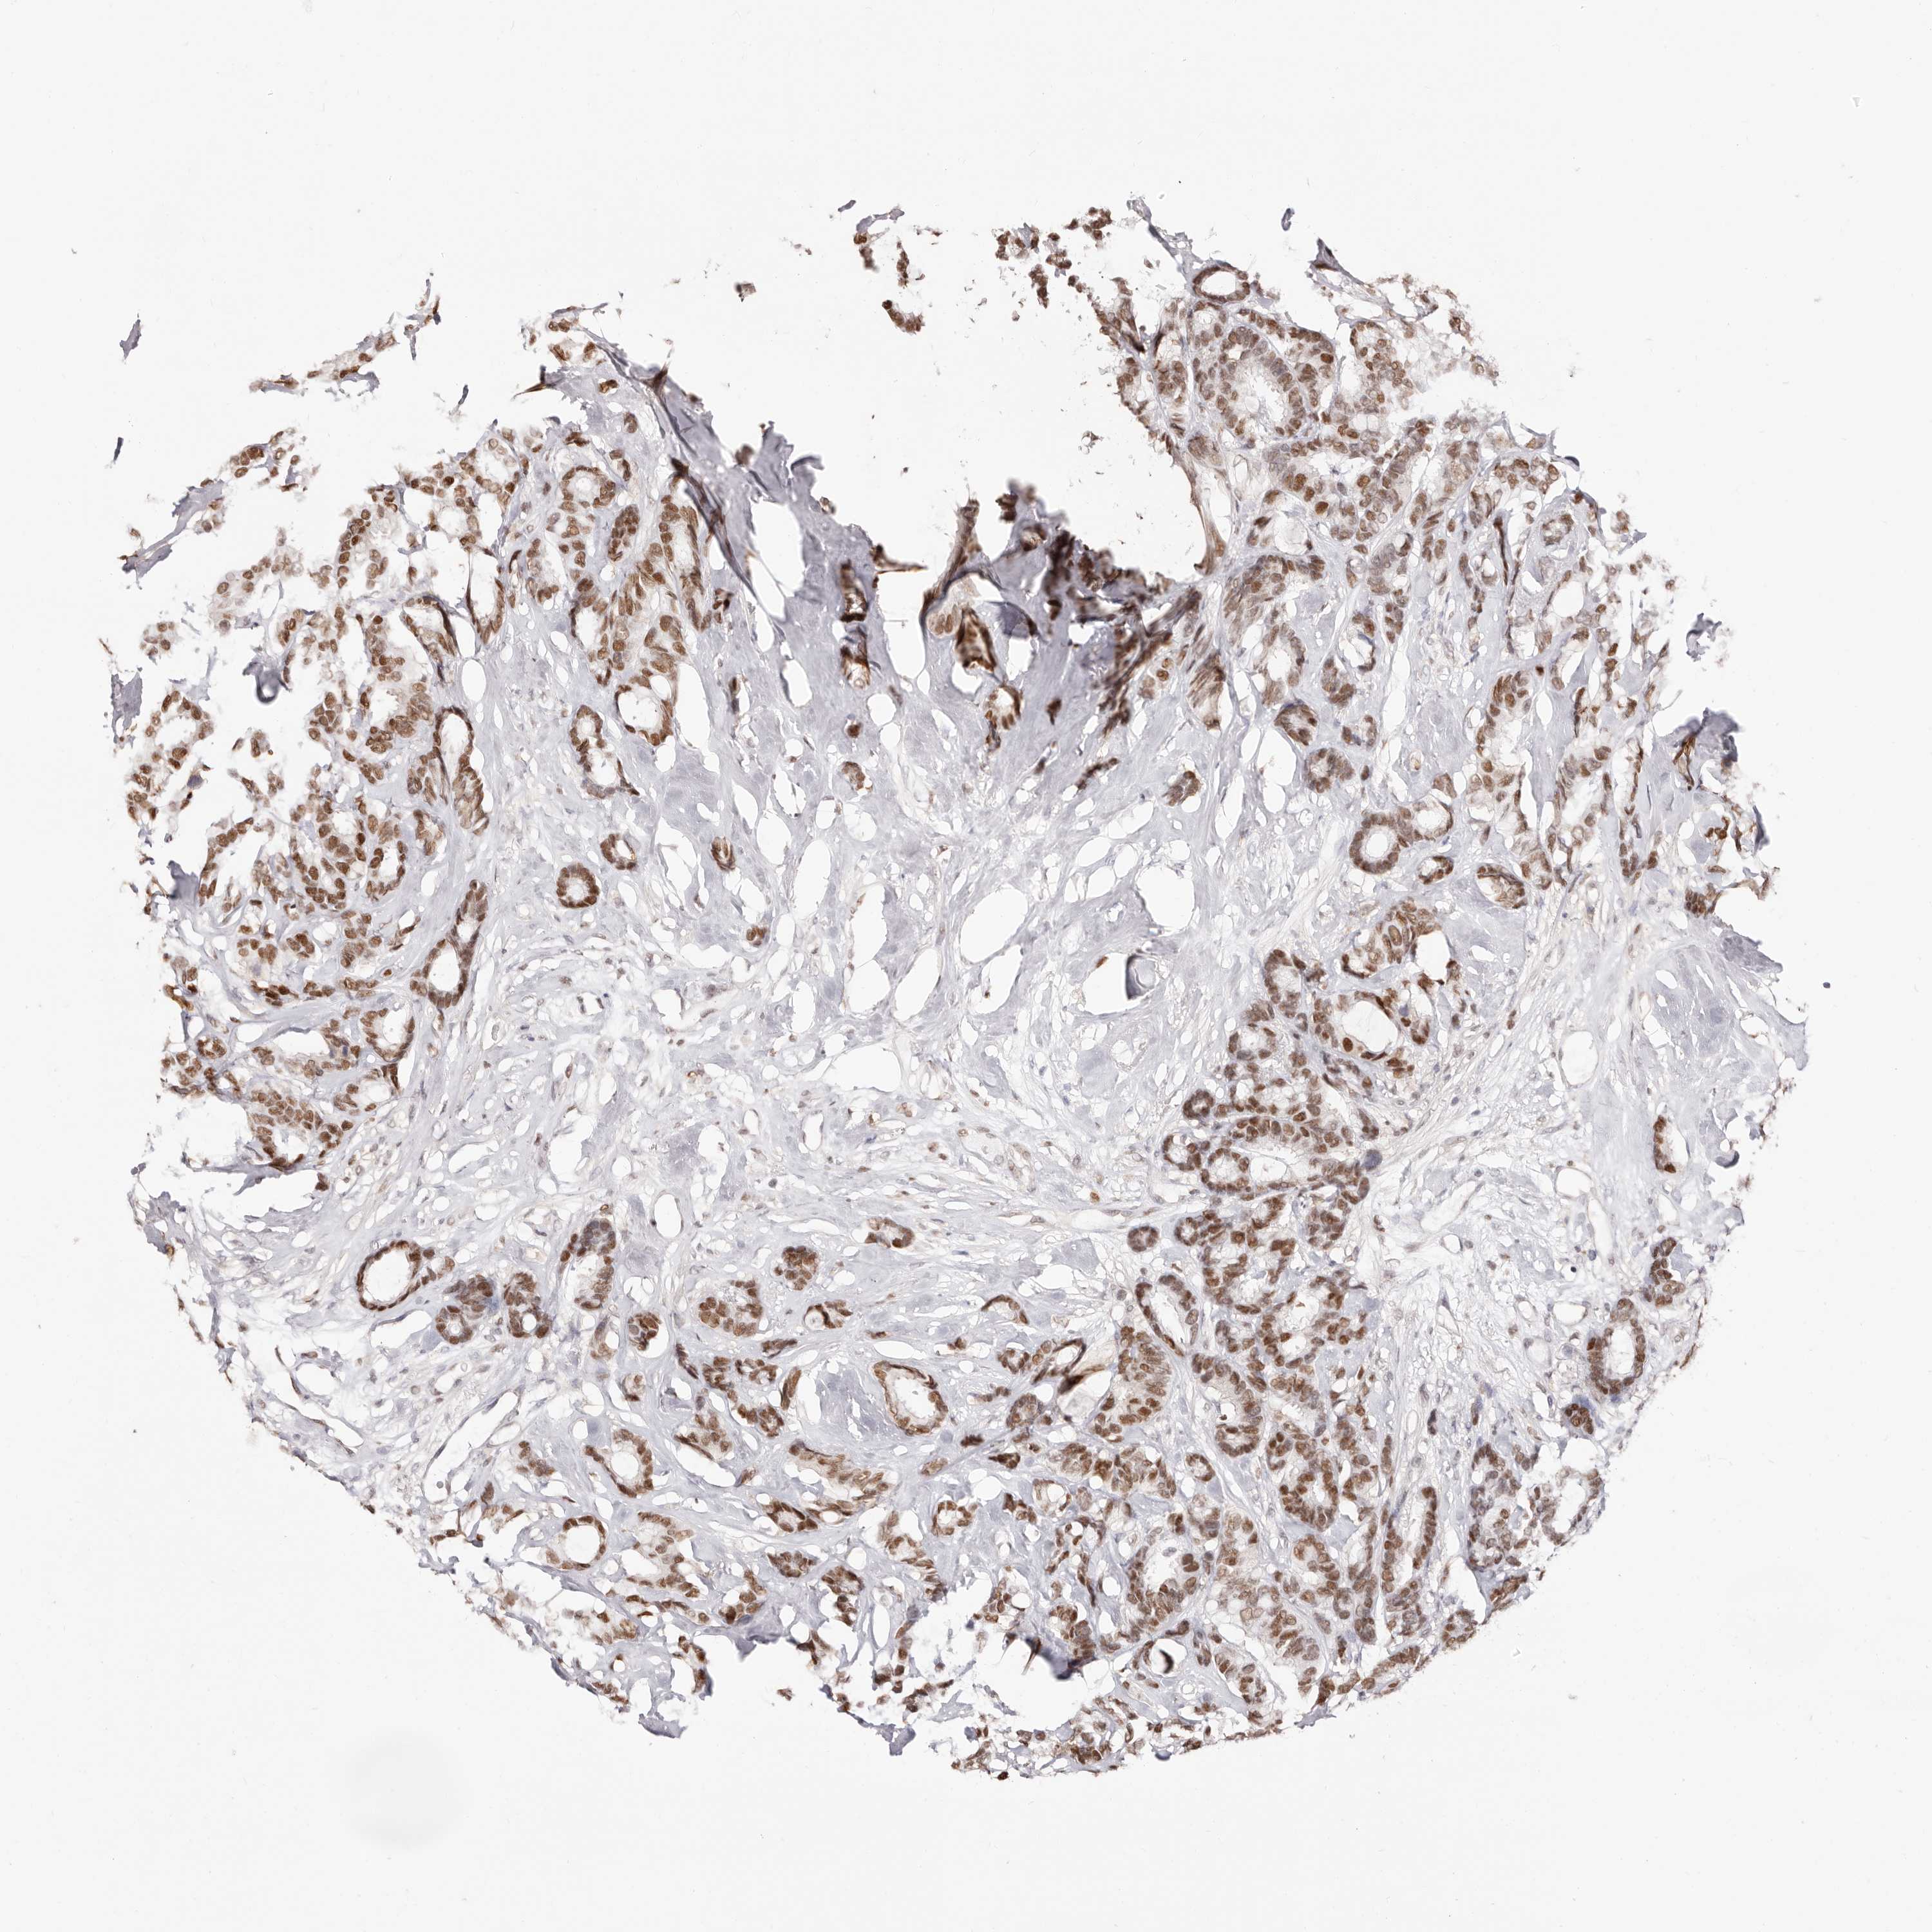

BRCA TCGA BRCA VALIDATION PROTEIN EXPRESSION